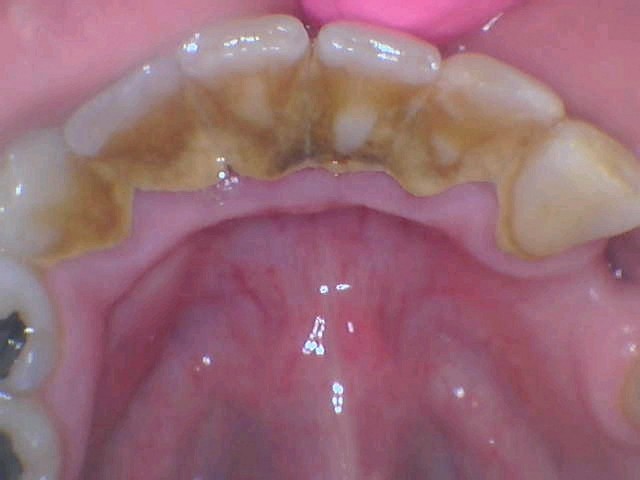

Periodontitis, also known as advanced gum disease, is a serious infection in your gums that damages your soft tissues. If not treated on time, it may destroy the bone supporting your teeth. This condition may also lead to tooth loss or loosening of your teeth from their sockets. Many factors add to the development of this disease; poor oral health is the most common of all.

- Scaling

Scaling removes the accumulation of tartar and bacteria from the surface of your teeth and beneath your gums. We perform it using a manual instrument. We may also use a laser to quicken the procedure.

- Root Planing

Root planing helps to smoothen the root surface, which further discourages the build-up of external elements. This step also removes bacterial byproducts contributing to inflammation or decay.